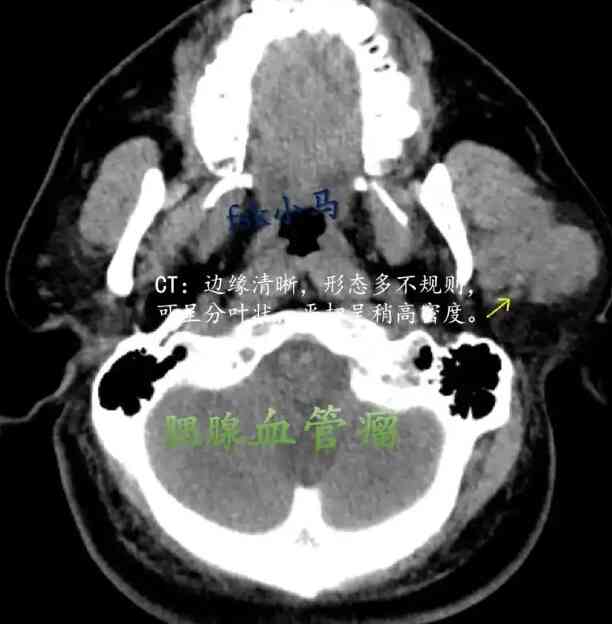

在这篇文章中,我们将探讨一个典型的病例。患者来自吉林省四平市,年龄50岁,身高176厘米,体重80公斤。检查显示,这名患者被诊断为腮腺瘤,但其具体的影像资料和详细数据暂未披露。临床上,他们接受了术前用药和各项麻醉剂量,准备进一步的手术治疗。

对于很多人来说,腮腺瘤可能是一个相对陌生的名词。腮腺瘤是一种发生在腮腺的良性肿瘤。通过本文,我们将为您详细解析腮腺瘤的潜在危害、治疗方法和预防措施。

腮腺瘤是腮腺细胞异常增生形成的肿瘤,通常是良性的。这种肿瘤最常见的症状是面部无痛性肿块。有时候,腮腺瘤也可能影响面神经,导致面部麻木或疼痛。虽然大多数腮腺瘤是良性的,但它们也有可能恶变为恶性肿瘤,因此需要及时诊断和治疗。